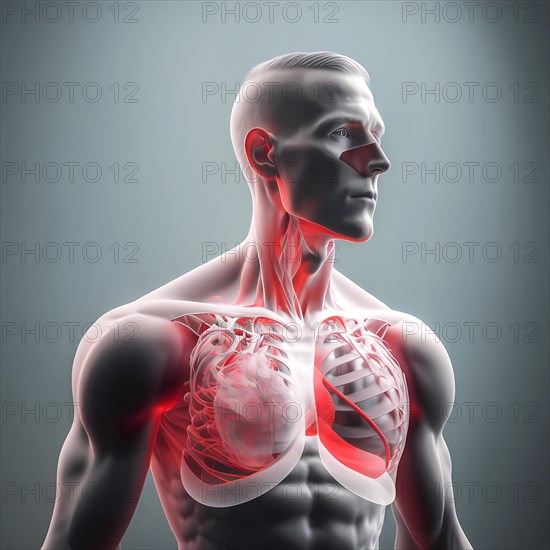

Sujet

**Image générée par intelligence artificielle**

Human transparent body icon with lungs, AI generated art image

1 person Ai generated Ai generated art bodies body body part body parts health illustration illustrations internal organ internal organs lung lungs medicine one person organ organs sheer single person transparent healthcare healthcare system medical medicinal